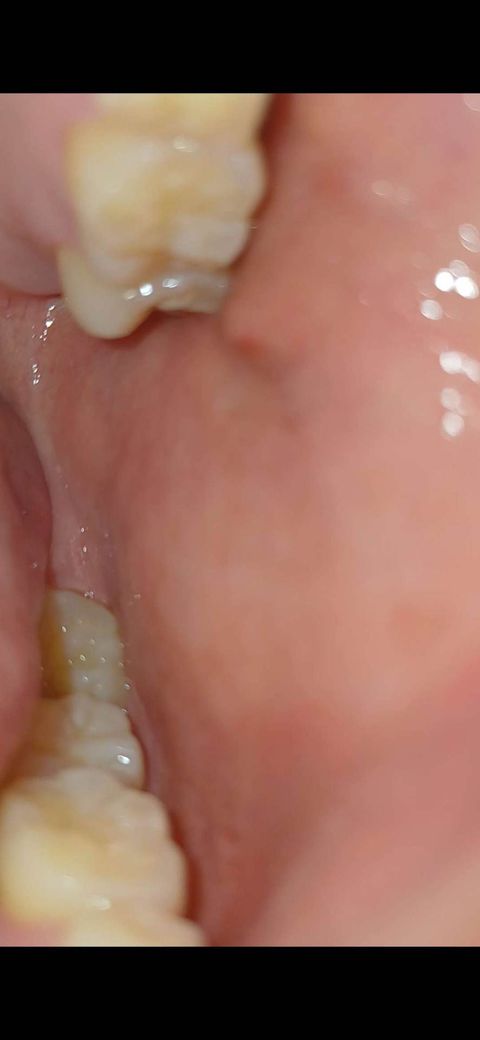

입안에 이빨옆쪽으로 부어올랐는데 뭘까요? 어디병원가야하죠

건들여도 딱히 아무런 통증도 없어요 왼쪽이 갑자기 이런데 딱히 이빨로 씹지도 않았고요

입 안열고 가만히 있으려고 해도 뭔가 부어올라서 그런가 불편하네요

사진으로 봤을 경우 구강 점막이 자극이 되어 붉게 된 것으로 생각됩니다. 음식을 먹을 때 너무 강한 힘으로 먹다보면 점막조직이 밀려. 치아 사이에서 씹히면서 사진과 같이 붉은색을 띨 수 있습니다. 해당 부위를 자극하지 않으면 대부분 일주일 정도 지나면 아물게 됩니다.

사진에 보이는건 볼살이 치아에 씹히거나 자극을 받아서 생기는겁니다. 큰 문제가 잇는건 아닙니다.

볼이 있는 부위라면 잘못씹히면서 부었을 가능성이 높습니다. 며칠 지나면 사라질겁니다.

타액선 염증이 있어 부었을 수도 있습니다 면역력저하, 컨디션이 안좋을 경우 일시적으로 그럴 수 있습니다